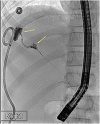

Blunt abdominal trauma is a common cause of solid organ injury in children. Nonoperative management has been established as the standard of care for suspected liver and spleen injuries without peritonitis. Major ductal injury with resultant biloma is a rare complication of nonoperative management of blunt liver injury. Endoscopic retrograde cholangiopancreatography (ERCP) and/or percutaneous drain placement are considered to be safe adjuncts in the management of these bile leaks. However, in the rare cases of persistent bile leak, further nonoperative alternatives have not been reported. In this case report we present a novel multidisciplinary approach to managing persistent bile leaks in blunt liver injury.